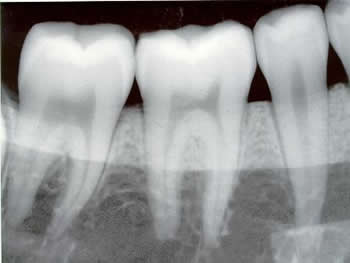

Digital Radiography

Dental Digital Radiography